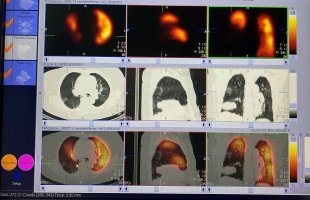

Przykładowe obrazy scyntygraficzne uzyskiwane w naszym Zakładzie Medycyny Nuklearnej: